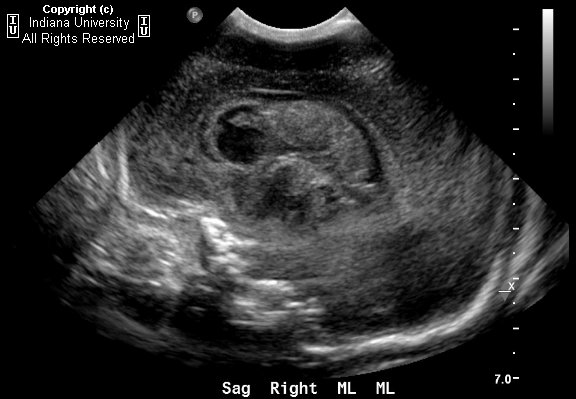

Germinal matrix hemorrhage is a bleeding into the subependymal germinal matrix with or without subsequent rupture into the lateral ventricle.

The germinal matrix is the site of proliferating neuronal and glial precursors in the developing brain, which is located above the caudate nucleus, in the floor of the lateral ventricle, and caudothalamic groove. The germinal matrix contains a rich network of fragile thin-walled blood vessels. Hence the microcirculation in this particular area is extremely sensitive to hypoxia and changes in perfusion pressure. It is most frequent before 35 weeks gestation and is typically seen in very low birth-weight (<1500g) premature infants,because they lack the ability for auto regulation of cerebral blood flow. Consequently increased arterial blood pressure in these blood vessels leads to rupture and hemorrhage into germinal matrix.

Four grades are distinguished (by imaging or histology):

- grade I - hemorrhage is confined to the germinal matrix

- grade II - intraventricular hemorrhage without ventricular dilatation

- grade III - intraventricular hemorrhage with ventricular dilatation

- grade IV - intraventricular rupture and hemorrhage into the surrounding white matter